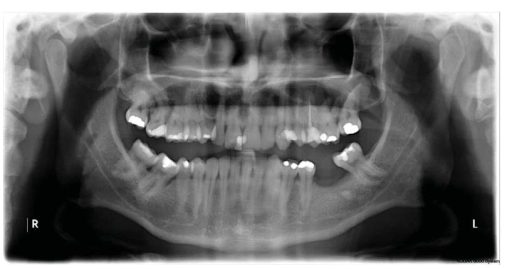

A 33-year-old man reported an episode of bleeding in the mouth and extravasation of fluid through the nose during liquid ingestion. The bleeding occurred in the upper right first molar region over one year, and there was extravasation of blood and serous fluid through the nose associated with pain and pressure on the same side of the face, when the patient was yawning. The medical condition did not show any comorbidity. In the intraoral exam, a 7mm periodontal pocket was detected. A gingival recession was also observed around the UFM and a Valsalva test was negative. The panoramic x-ray showed vertical bone loss in the super right first and second molar (URFSM) region. There was a bilateral alveolar ex-tension of maxillary sinus with opacification on the right maxillary sinus only (figure 2). We prescribed a CBCT exam, which showed severe furcation in-jury, external root reabsorption and vertical bone loss around cortical floor, and a thickening of the sinus mucosa around the URFSM. There was a rupture in the floor of the cortical sinus (figure 3). The diagnostic hypothesis was OMS related to periodontal disease or maxillary sinus tumor of the maxillary sinus floor. The extraction of the URFSM was done with curettage of the soft tissue associated with dental roots. In the surgical procedure, a 1cm diameter oroantral communication was observed, treated with intra alveolar fibrin sponge covered with a vestibular flap of oral mucosa (figure 4). The microscopic analysis showed no signs of malignancy and chronic inflammatory cell infiltrate compatible with inflammatory periodontal disease (figure 5). The final diagnosis was odontogenic maxillary sinusitis related to periodontal disease. A corticosteroid nasal spray was prescribed, and three months after the surgical procedure no clinical signs or symptoms were observed. A new panoramic x-ray six months after the surgical procedure showed normal radiopacity of the right maxillary sinus (figure 6).